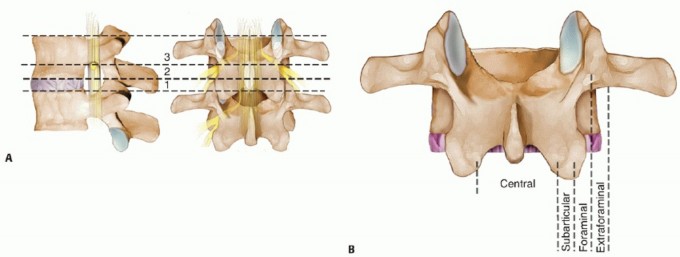

DEFINITION Cervical radiculopathy is a clinical diagnosis defined by the presence of motor or sensory changes…

Evaluation of Nerve Root Lesions Involving the Upper Extremity Examination by neurologic level is based on th…

Clinical Application of Neurologic Levels Herniated Cervical Disks There are eight cervical nerves and only s…